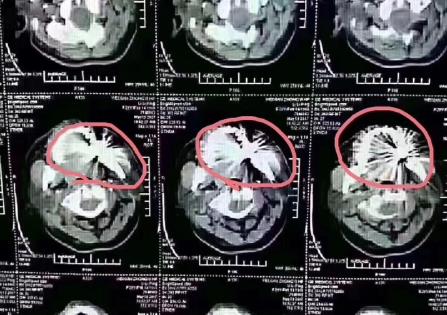

不同的金屬牙冠產(chan) 生的偽(wei) 影